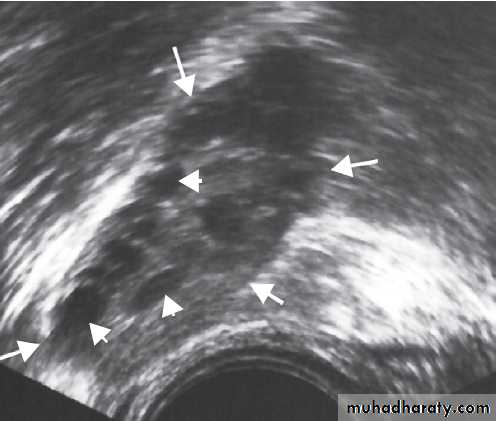

Thyroid ultrasound

If thyroid function tests are normal, an ultrasound scan

will determine the nature of the thyroid swelling. Ultrasound

can establish whether there is generalised or localised swelling of the thyroid. Inflammatory disorders

causing a diffuse goitre, such as Graves’ disease

and Hashimoto’s thyroiditis, demonstrate a diffuse

pattern of hypoechogenicity and, in the case of Graves’

disease, increased thyroid blood flow may be seen on

colour flow Doppler. The presence of thyroid autoantibodies

will support the diagnosis of Graves’ disease or

Hashimoto’s thyroiditis, while their absence in a younger

patient with a diffuse goitre and normal thyroid function

suggests a diagnosis of ‘simple goitre’ .

Ultrasound can also readily determine the size and

number of nodules within the thyroid and can distinguishsolid nodules from those with a cystic element.

It cannot reliably distinguish benign from malignant

nodules but, in experienced hands, there are some

ultrasound characteristics which are associated with a

higher likelihood of malignancy. These include: hypervascularity of the nodule, the presence of microcalcification and irregular, infiltrative margins.

A pure cystic nodule is highly unlikely to be malignant and a ‘spongiform’ appearance is also highly predicative of a benign aetiology.